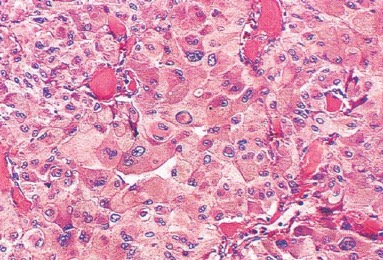

1076. Параганглиома, показанная на микрофотографии, чаще всего развивается в